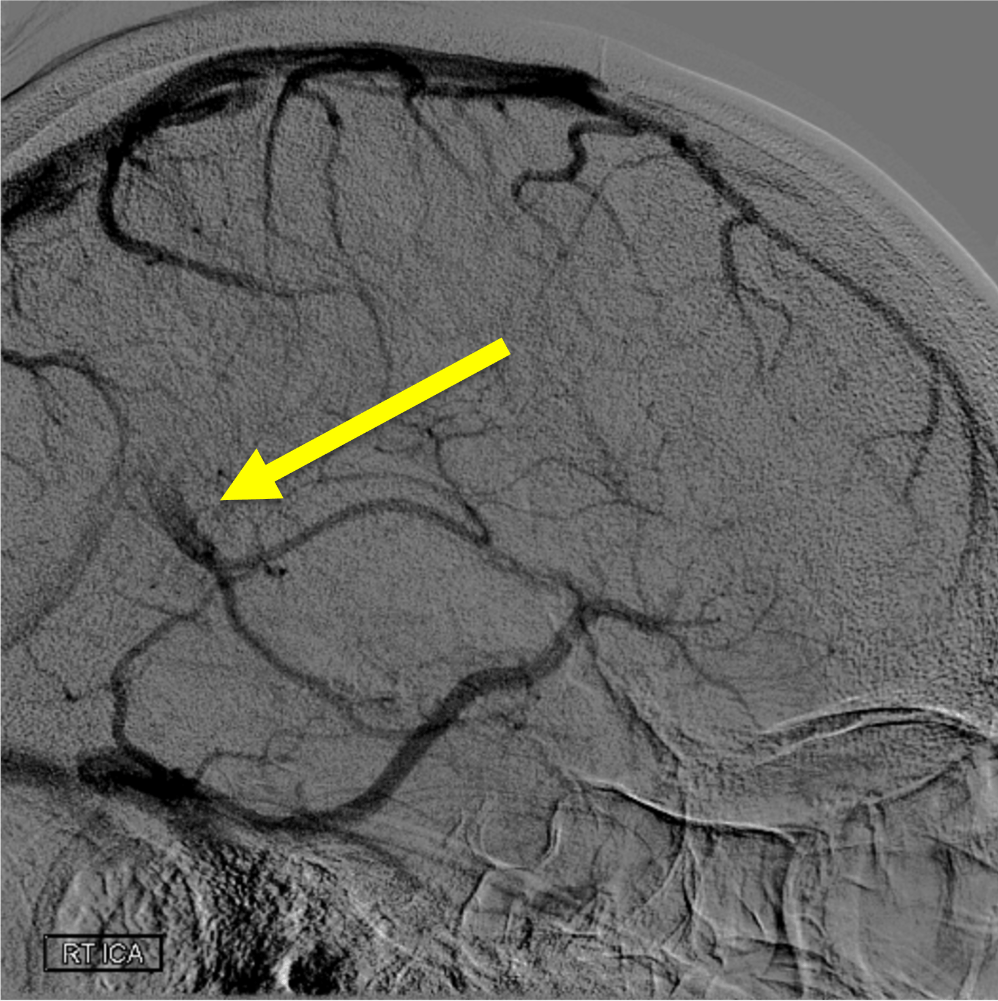

On this lateral view R ICA injection, name these two branches:

Pericallosal and callosomarginal arteries off the ACA